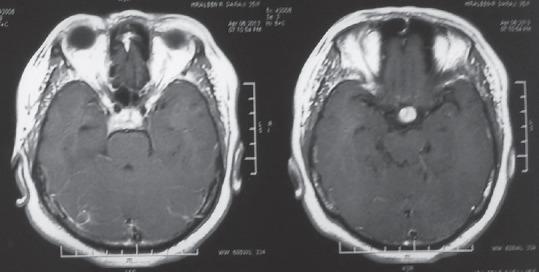

Isolated sellar tuberculoma is a very rare condition and usually presents with headache and decreased vision. It can present with panhypopituitarism with 3 nerve palsy. Tuberculoma mimics pituitary adenoma clinically as well as radiologically and requires endoscopic transsphenoidal surgery and histopathological examination for the final diagnosis. We present a rare case of a 40-year-old female presented with headache, decreased vision, and unilateral 3 nerve palsy with panhypopituitarism.

孤立性鞍区结核瘤是一种非常罕见的病症,通常表现为头痛和视力下降。它可伴有全垂体功能减退及动眼神经麻痹。结核瘤在临床和影像学上都酷似垂体腺瘤,最终诊断需要经鼻蝶窦内镜手术及组织病理学检查。我们报告一例罕见病例,一名40岁女性,表现为头痛、视力下降、单侧动眼神经麻痹伴全垂体功能减退。